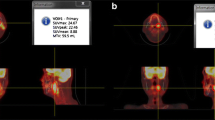

Representative cases

Figures 1 and 2 show representative cases in this study. Figure 1 shows a 51-year-old man with right tongue cancer (T4aN0M0, Stage IVA). 18F-FDG PET/CT scans showed intense accumulation of 18F-FDG (PET parameters: SUVmax, 4.2 g/ml; SUVpeak, 3.3 g/ml; MTV, 3.4 g/ml; TLG, 10.6 bw × cm3) (Fig. 1c); however, 18F-FAMT scans did not show intense accumulation (PET parameters: SUVmax, 1.7 g/ml; SUVpeak, 1.5 g/ml; MTV, 1.2 g/ml; TLR, 1.8 bw × cm3) in this patient (Fig. 1d). The patient outcomes were censored. Figure 2 shows a 63-year-old man with right tongue cancer (T2N2bM0, Stage IVA). 18F-FDG PET/CT scans showed intense accumulation of 18F-FDG (PET parameters: SUVmax, 6.4 g/ml; SUVpeak, 4.4 g/ml; MTV, 5.0 g/ml; TLG, 18.2 bw × cm3) (Fig. 2c), and 18F-FAMT scans also showed intense accumulation (PET parameters: SUVmax, 2.3 g/ml; SUVpeak, 1.8 g/ml; MTV, 6.1 g/ml; TLG, 10.5 bw × cm3) in this patient (Fig. 2d). The patient outcome was local recurrence (160 days postoperatively).